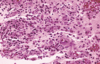

chronic hyperplastic pulpitis

chronic hyperplastic pulpitis